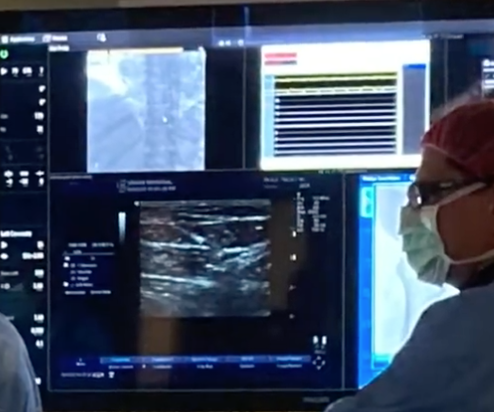

Interventional Cardiology →

The mission of the Interventional Cardiology Fellowship Program is to provide cutting-edge care for patients with cardiovascular disease, utilizing evidence-based medicine and state-of-the-art interventional technology. Fellows will be trained within the diverse and high-volume cardiac population of Central Massachusetts.

Clinical Cardiac Electrophysiology →

The mission of the Clinical Cardiac Electrophysiology Fellowship Program is to train fellows to become competent and confident clinical cardiac electrophysiologists. The program provides exposure to all aspects of clinical electrophysiology including the evaluation and diagnosis of cardiac dysrhythmias, treatment and post-op care. Fellows will combine this experience with active didactic education and attendance and participation in local, regional and national education forums. Our program also offers fellows with the opportunity to explore clinical research and pursue leadership roles within the diverse and high-volume cardiac population of Central Massachusetts.